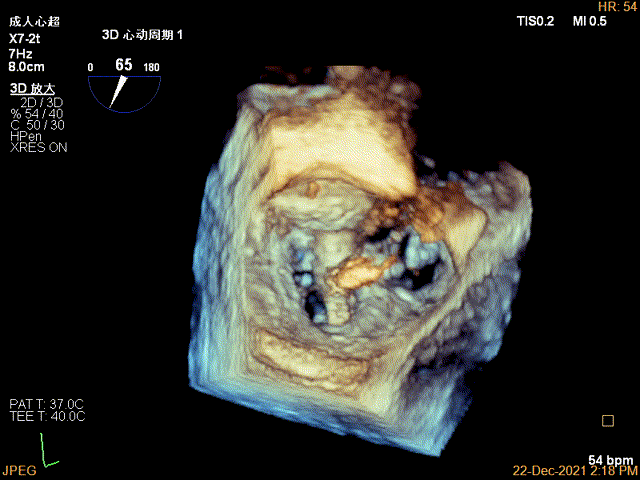

3D MV View:P2区脱垂

3D-color MV view:大量反流,起源于2区

Qlab软件勾画估测瓣口面积约:7.19cm²

3D-VIEW验证前后叶抓捕情况,可观察到第一个夹子外侧的残余脱垂

3D-color-VIEW验证残余分流,位于第一个夹子外侧

3D-VIEW提示第二个夹子置于第一个夹子外侧,并呈平行关系

3D-VIEW验证抓捕结果

3D-color-VIEW验证残余分流近消失